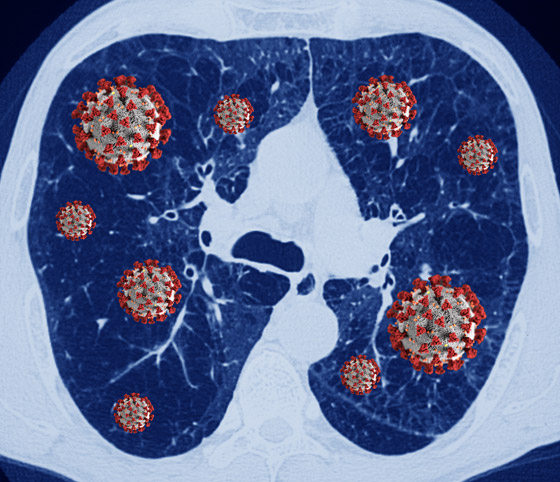

تصوير مقطعي محوسب من مستشفى جامعة جورج واشنطن يُظهر آثار فيروس كورونا المستجد، أو ما يُعرف بـ"كوفيد-19"  رئتي رجل عمره 59 عاماً. فشاهدوا معنا في الفيديو المدهش أدناه كيف تبدو رئة مصاب بفيروس كورونا (فيروس كوفيد 19) وما يحصل داخلها..